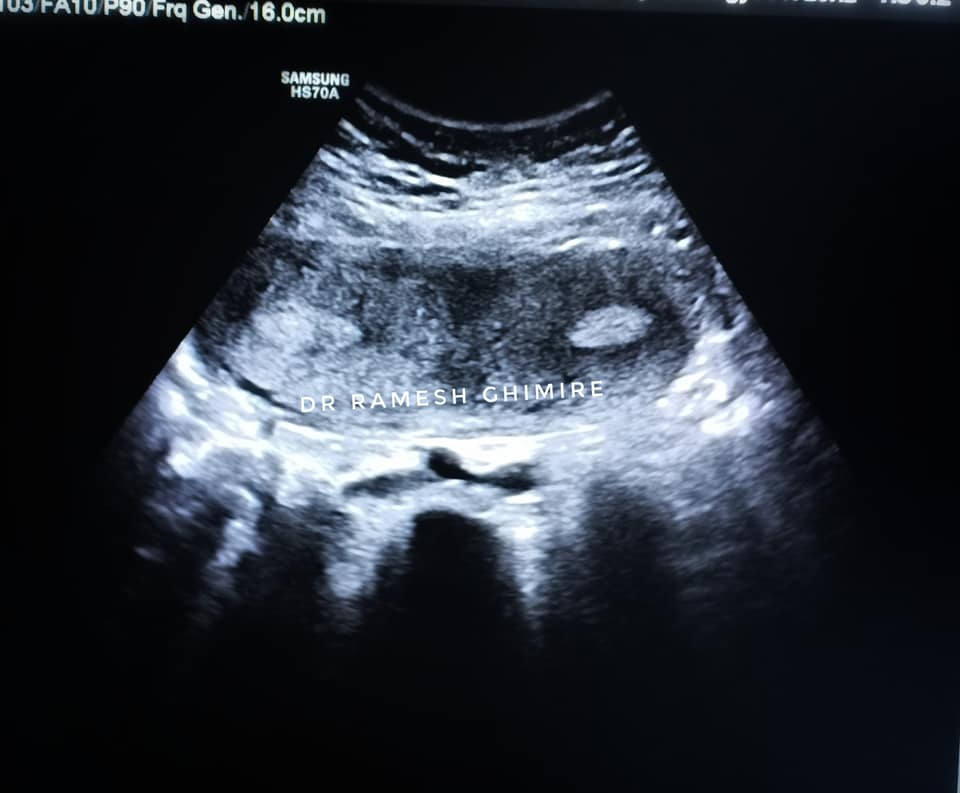

गर्भमा बच्चा नबसेको भन्दै आएकी एक महिलाको शरिरमा दुईवटा पाठेघर भेटिएको डा रमेश घिमिरेले लोकपथलाई जानकारी दिए । ती महिलाको शरिरमा भएको दुई वटा पाठेघर ‘४डी’ टेक्नोलोजीमार्फत पत्ता लागेको उनले बताए । त्यस्ता केसहरु आइरहने पनि उनले बताएका छन् । “प्राय यस्ता केसहरु आइरहेका हुन्छन् । तर त्यसको पहिचान ४डी प्रविधिबाट मात्रै पहिचान गर्न सकिन्छ ।” उनले भने ।

साथै ४ डी प्रविधि राख्नका लागि बढी खर्च हुने भएकाले धेरै अस्पतालहरुमा त्यसको पहुँच नभएको उनको भनाइ छ । नेपालका सिमित अस्पतालहरुमा मात्रै यस्तो प्रविधि भएको र चितवनमा भने मौलाकालिका अस्पतालले नै पहिलो पटक उक्त प्रविधि भित्र्याएको दाबी गरे ।